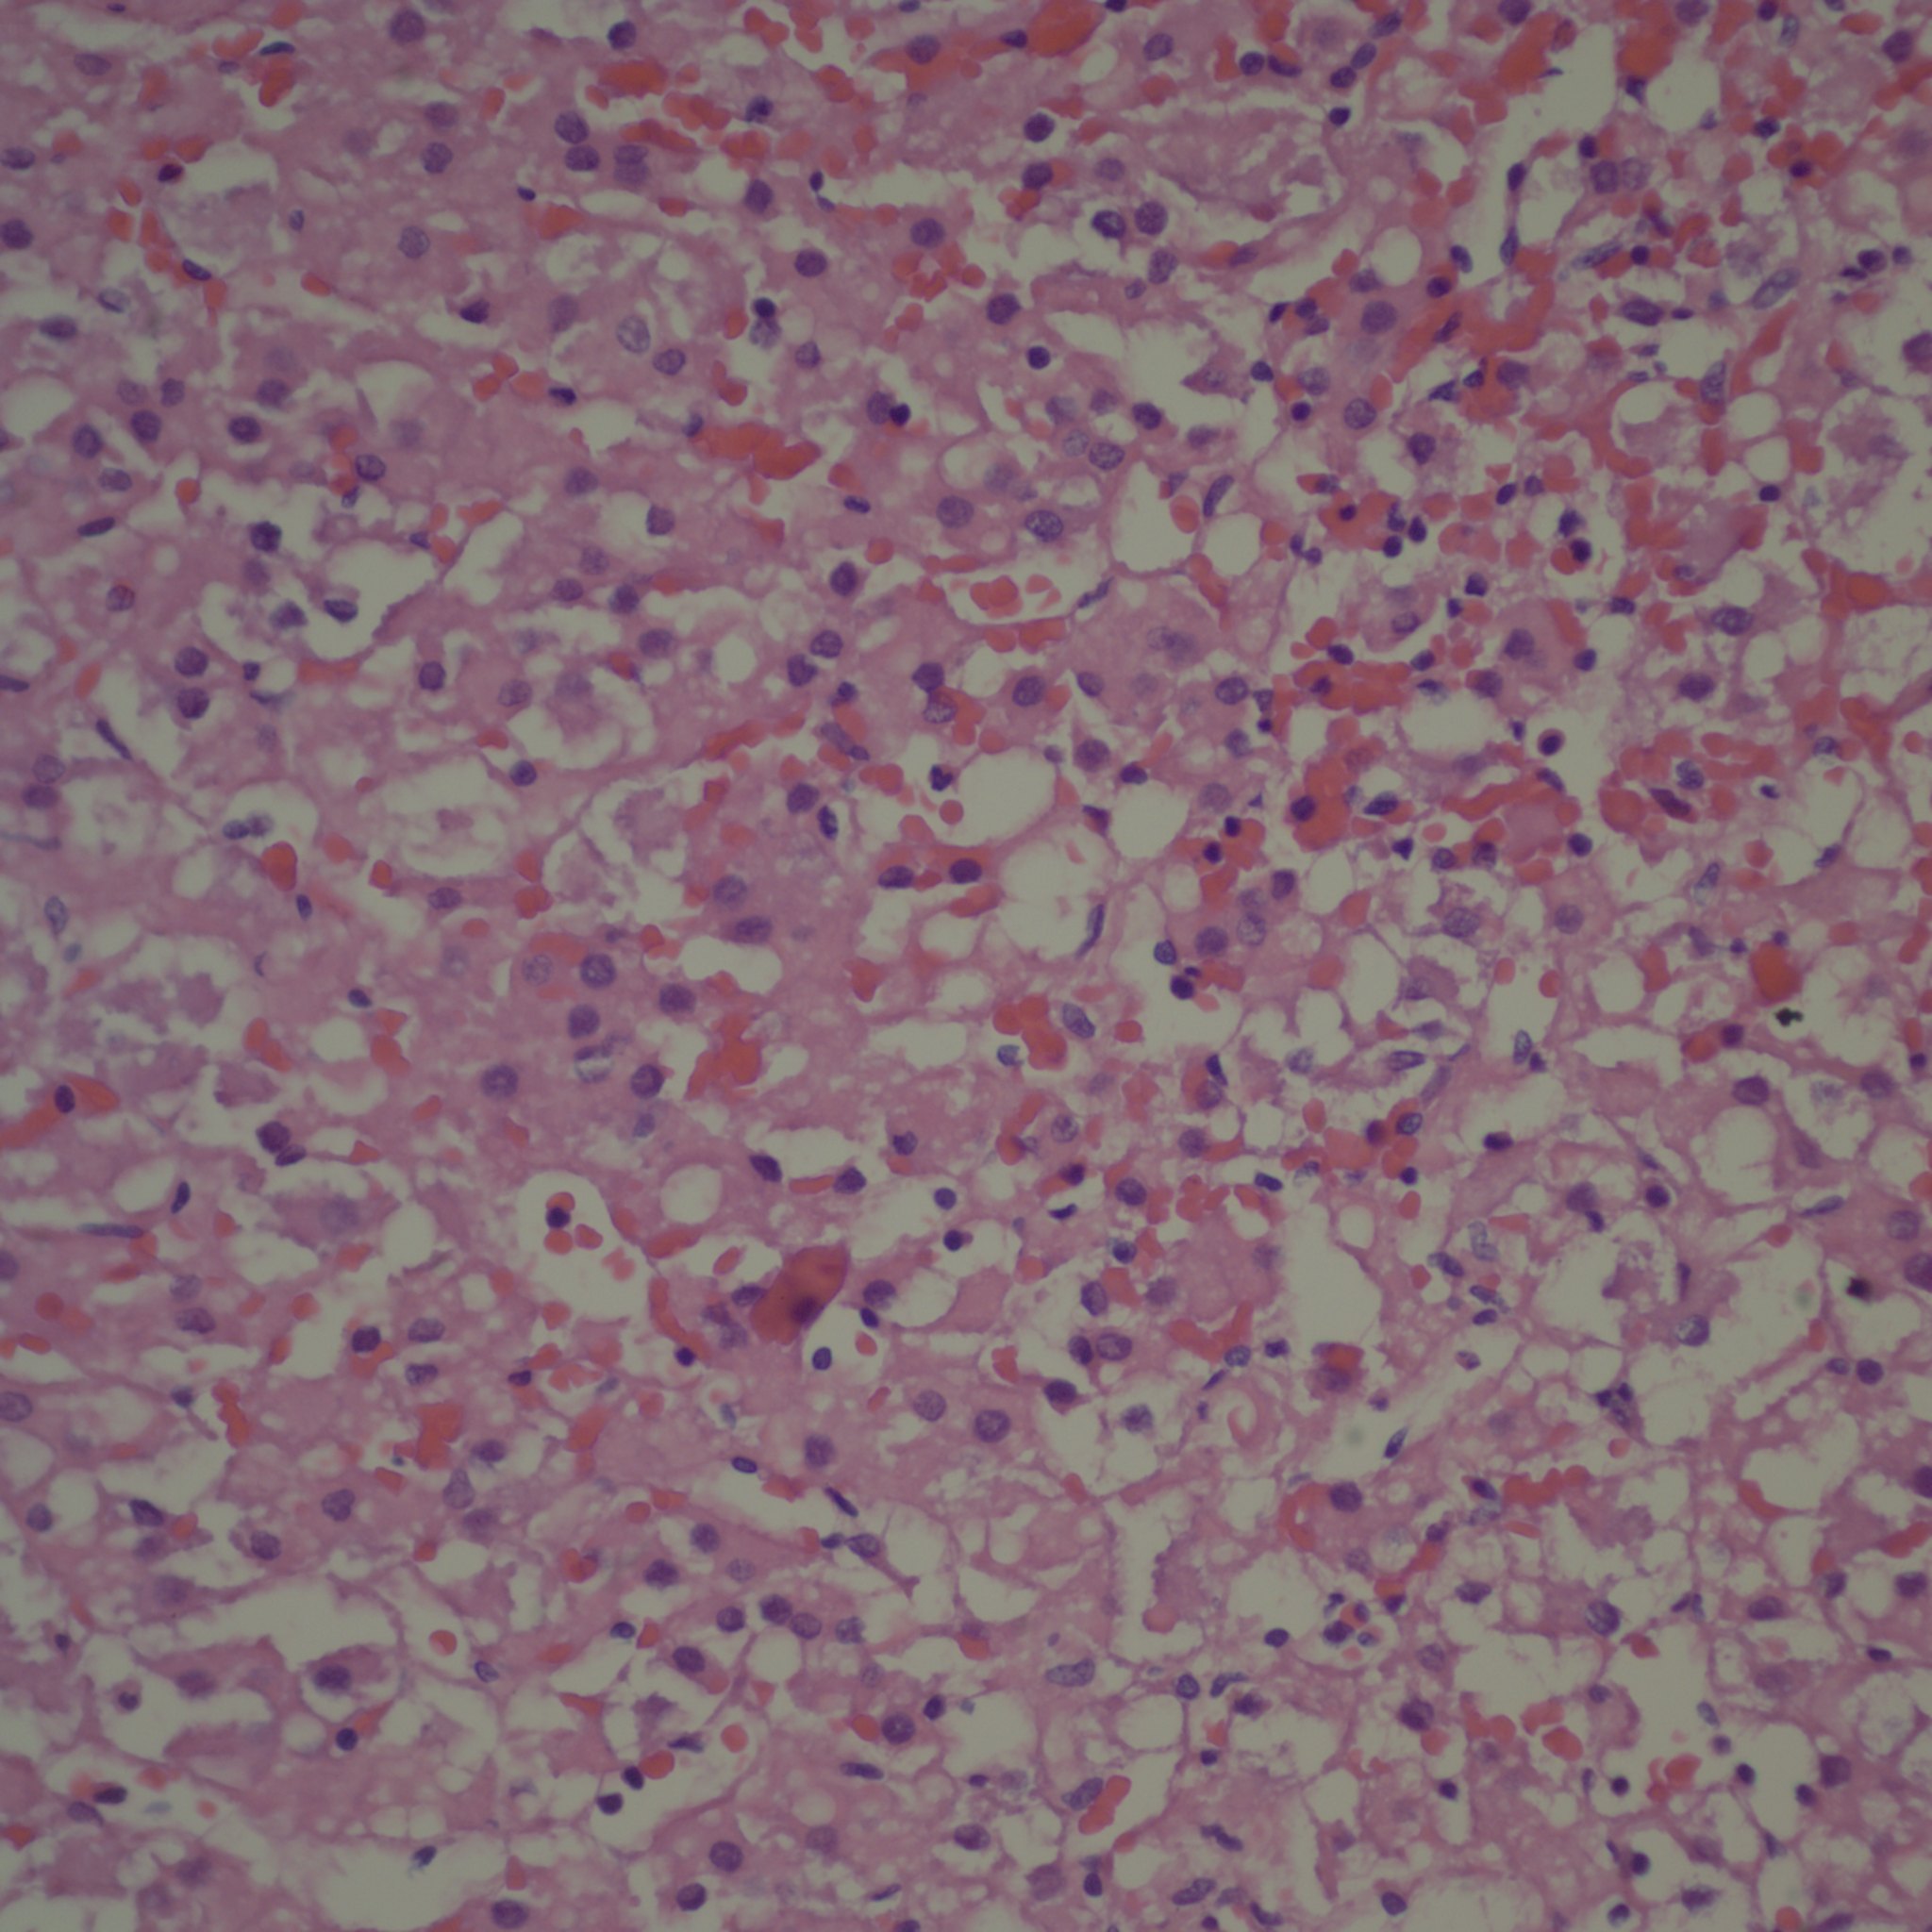

Because of the previous blog, a colleague Dr. Jeff Goldstein kindly shared a case of a 30 hour old infant with profound involution of the fetal zone of the cortex and prominent lipid in the permanent cortex, who died of severe congenital pulmonary malformation. The thymus did not show accelerated involution.

How is the involution of the fetal zone cortex controlled after birth? The biochemical evidence is that it ceases to function almost immediately although it takes days to weeks to demonstrate histologic involution. Some older papers suggested that HCG was trophic for fetal zone cortex, but not sufficient without ACTH to produce growth of this zone. Thus withdrawal of HCG with birth could be the signal for the involution of the fetal zone. If so there should be a correlation with Leydig cell involution which is HCG dependent (a luteinizing hormone analog). I searched my database for the lowest adrenal to brain ratio cases, and in the most extreme case, indeed there were no Leydig cells and the fetal zone had accelerated involution. This was a growth retarded 36 week gestation triplet infant without a clear cause of death at 30 minutes of life. I have no idea why this effect occurred, but these cases demonstrate that there are still mysteries to be solved.